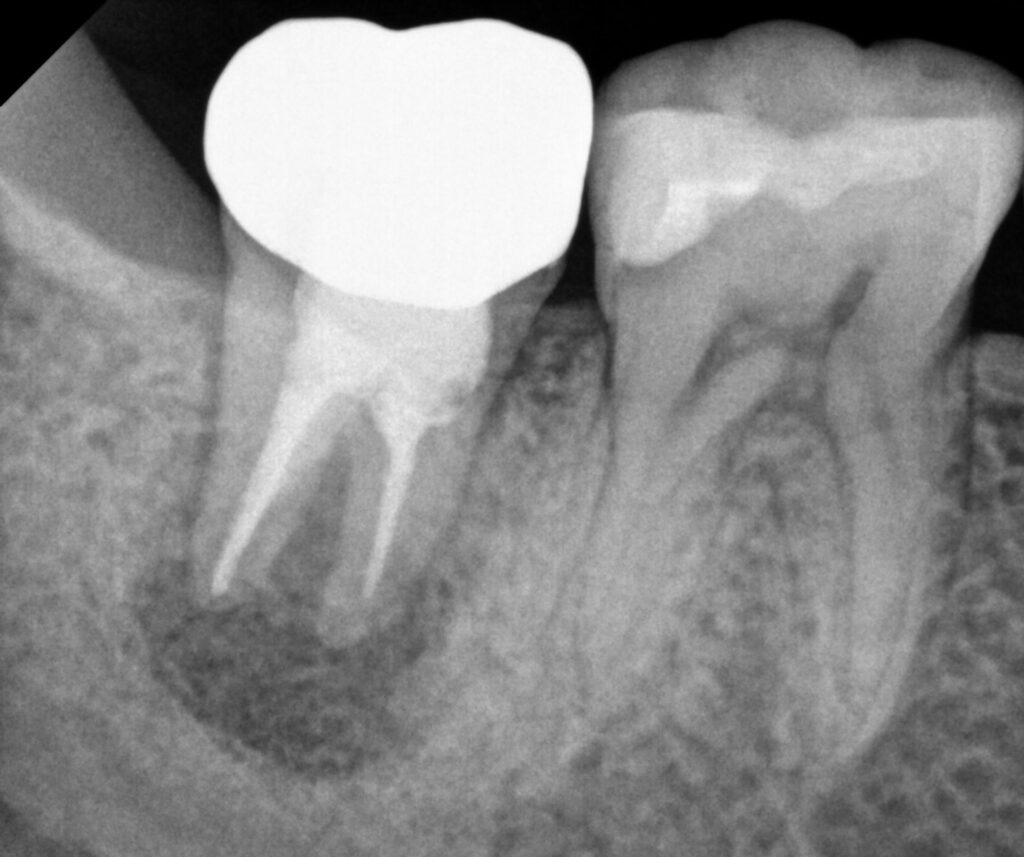

치아재식술 후 4개월까지 경과 모습으로,

엑스레이 사진에서는 기존 염증 부위가

점점 건강한 뼈조직으로 채워지고 있는 것을

명확하게 확인할 수 있습니다.

치조골이 생성되면서

동요도가 사라졌고 불편했던 느낌도

모두 해결된 것을 확인할 수 있습니다.

이는 재식술이

성공적으로 이루어졌음을

보여주는 소견이었습니다.

이번 케이스에서 주목할 점은

재 신경치료 시에는

치근단까지 근관충전이

잘 이루어지만,

자연치의 C형 해부학적 구조로 인해

오목한 부위에 채워진 염증조직이

자연 치유되지 않았던 것이

지속적인 통증의 원인이었습니다.

일반적인 근관치료로는

이러한 특수한 부위에

접근하기가 어렵습니다.

재식술을 통해

구강 밖에서 직접적으로

문제 부위를 확인하고

오목한 부분의 염증을 제거한 후

MTA로 밀봉함으로써

주변에 정상적인 조직이

형성될 수 있는 환경을

만들어 줄 수 있었습니다.